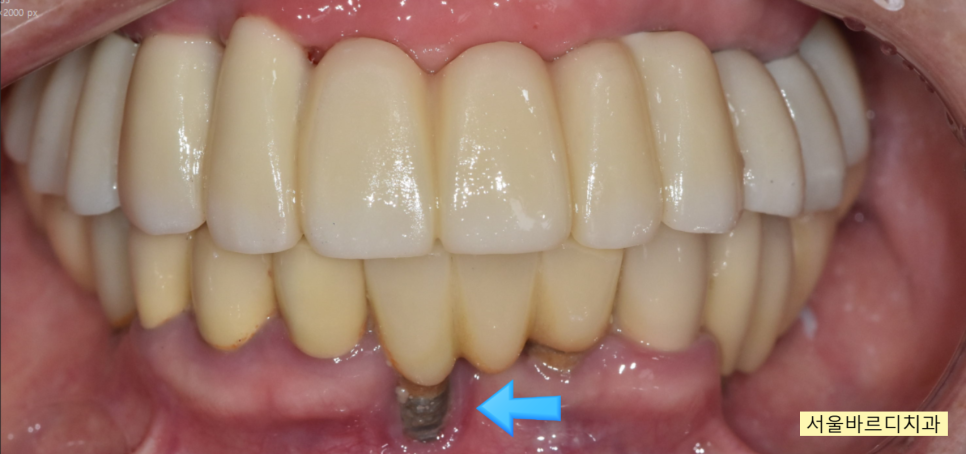

250314

치료가 끝난 모습입니다.

윗니가 아랫니를 덮는

정상적인 교합으로 마무리 되었습니다.

입술을 씹는 문제는

자연스럽게 해결~~

예전에 심어둔 임플란트 부분이 잇몸뼈가 녹으면서

노출되었는데

이것은 관리해가면서 최대한 쓰시기로 하고...